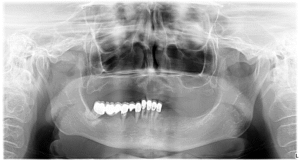

Acesta a fost și cazul pacientei noastre care, atunci când s-a prezentat la consultația inițială, nu mai avea deloc dantură la maxilar, ceea ce nu ne-a dat de ales, decât să apelăm la această tehnică.

În timpul intervenției chirurgicale au fost inserate 4 implanturi zigomatice în maxilar, și 4 implanturi convenționale la mandibulă. Acestea au fost suficiente pentru a susține o dantură completă și funcțională!